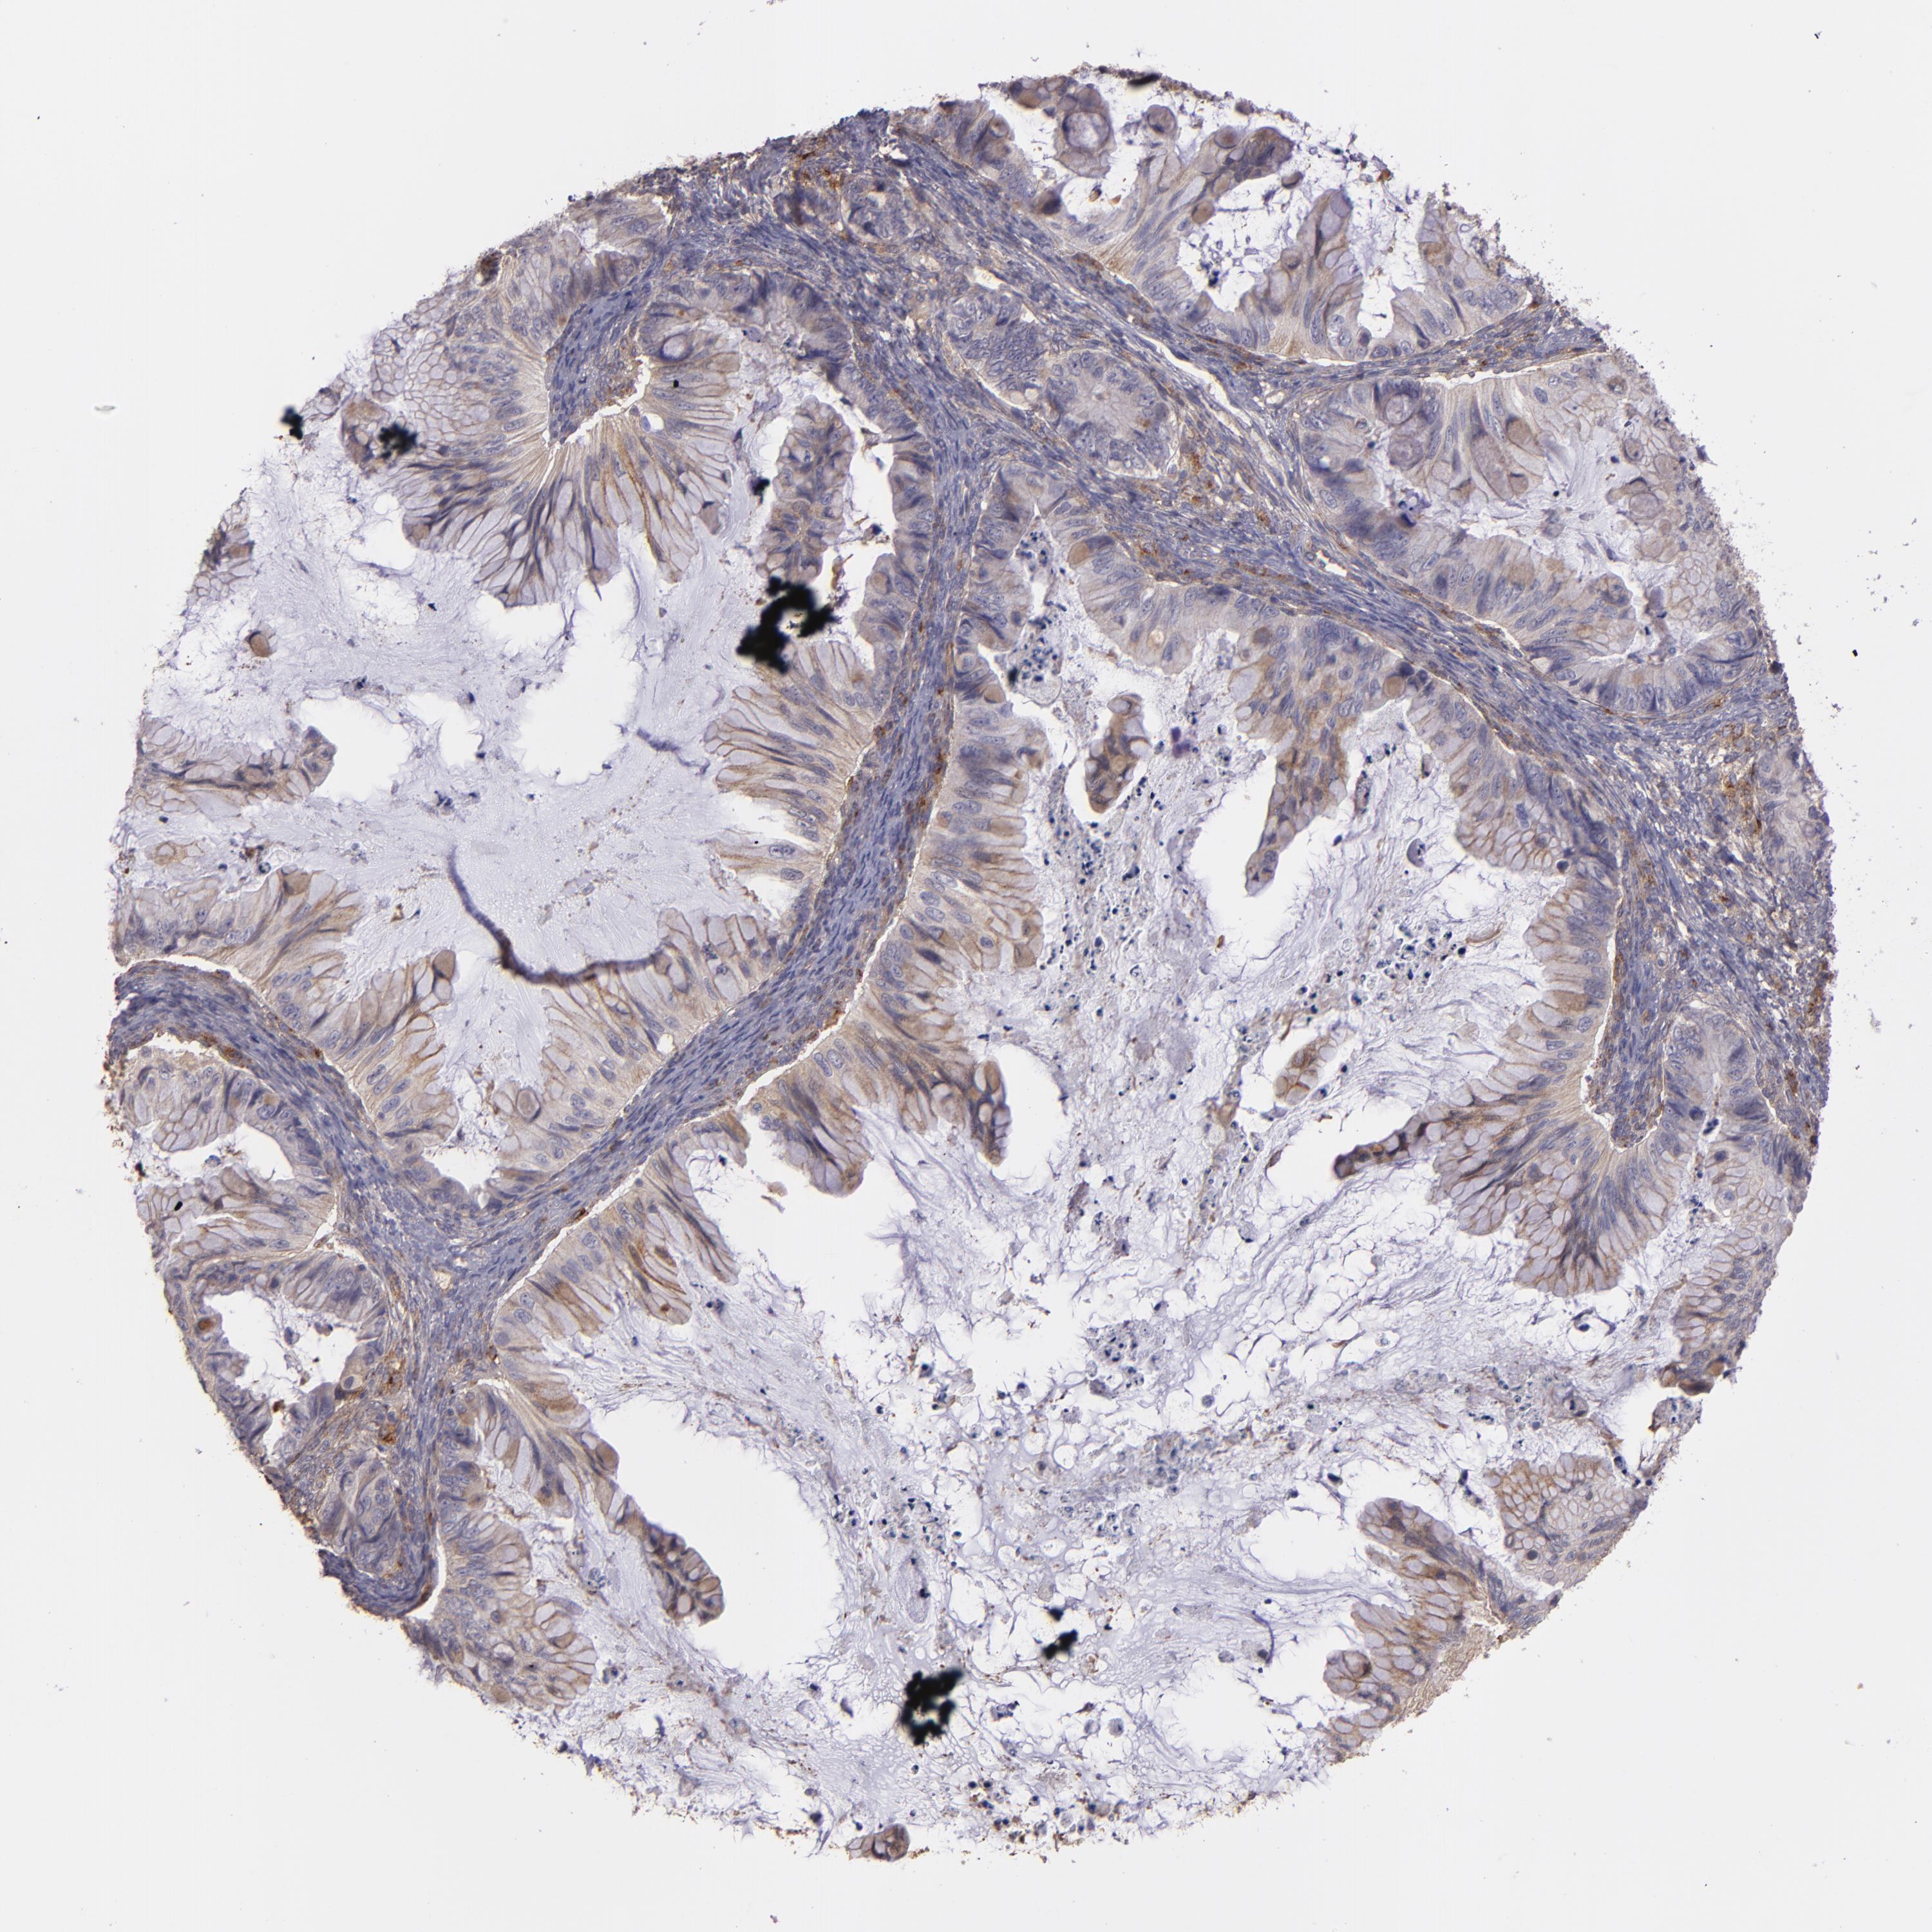

OVARIAN CANCER - Protein expressioni

A mouse-over function shows sample information and annotation data. Click on an image to view it in a full screen mode. Samples can be filtered based on level of antibody staining by selecting one or several of the following categories: high, medium, low and not detected. The assay and annotation is described here.

Note that samples used for immunohistochemistry by the Human Protein Atlas do not correspond to samples in the TCGA dataset.

Antibody stainingi

Antibody staining in the annotated cell types in the current human tissue is reported as not detected, low, medium, or high, based on conventional immunohistochemistry profiling in selected tissues. This score is based on the combination of the staining intensity and fraction of stained cells.

Each image is clickable and will lead to virtual microscopy that enables deeper exploration of all samples and also displays staining intensity scores, fraction scores and subcellular localization as well as patient and tissue information for each sample.

Antibody HPA001490

Cystadenocarcinoma, mucinous, NOS

Carcinoma, endometroid

Cystadenocarcinoma, serous, NOS

Carcinoma, NOS